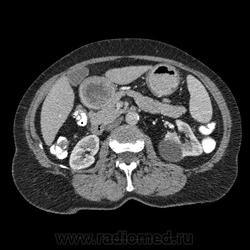

Впечатление, что дуля эта вне головки п.ж., интрамурально в луковице, что ли... тогда возможно GIST, но надо дайком. Утолщение подслизистой в антральном отделе желудка, не удается проследить переход от желудка к 12-перстной((. Внутрипросветно/внутристеночно - не разобрать. 1 фаза?

Клинику! Есть ли признаки высокой тонкокишечной непроходимости, что при ФЭГДС в 12-перстной - туда удалось пройти или нет? ААА! Одни вопросы))))

В-общем, варианты такие без дайкомов: пролапс слизистой в 12перстную, безоар, внутрипросветный дивертикул, гастроинтерстинальная опухоль. И большие сомнения, что это в головке п.ж. - оно отделено от неё тонким слоем жировой клетчатки

Фаз было 3. Видео не выставлял прошлый раз пришел ответ из сайта что видео не работает на сайте Идет накопление контраста в нативе в центре +2+4 по периферии +32+34 .в артериальную +20 и +65 +70 соответственно.

Что оно копит - бог с ним... если это пролапс слизистой, то суммация стенок. Безоар бы не копил. Напрягает отек слизистой в антрале... Это должно быть скорее внутри просвета кишки, т.к. оттесняет газ в 12-перстной на периферию. Без дайкомов больше ничем не могу, извините. Подождём мнения коллег.

Как мне видится - пролапс слизистой желудка в 12-перстную. А мнения коллег что-то нетути...

А что растет из левой почки? Может оно же и желудок сдавливает?

Это расширение всей 12- перстной кишки (стаз).